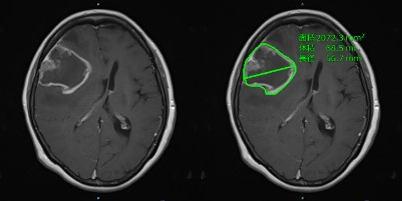

日本國立癌癥研究中心聯(lián)手日本富士膠片開發(fā)AI技術(shù)以提高神經(jīng)膠質(zhì)瘤圖像評估的準(zhǔn)確性

概述日本國立癌癥研究中心和日本富士膠片株式會社已經(jīng)共同開發(fā)了從MRI圖像中精確提取神經(jīng)膠質(zhì)瘤數(shù)據(jù)的人工智能... -